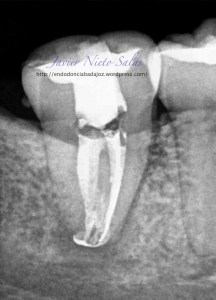

Se trata de una caso con una clasificación Tipo IIIb por el método de Min, ya pudimos sospechar que se trataba de un conducto en C:

Así podemos modificar nuestra técnica de obturación sabiendo que se trata de un sistema de conductos complicados